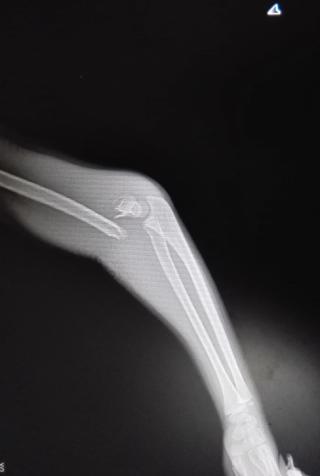

典型病例:中醫(yī)手法整復,夾板固定治療肱骨髁上骨折